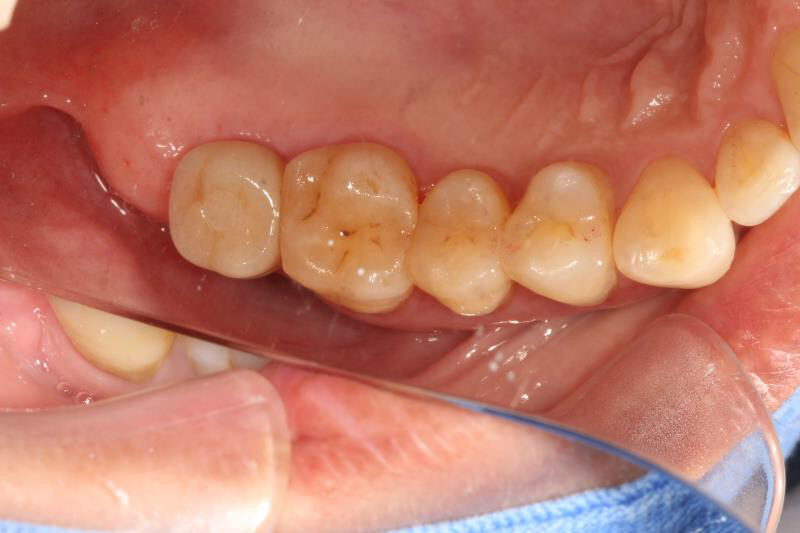

今天给大家分享的病例是一位中年女性,17缺失,由于长时间未修复,47伸长,留给17修复的空间不足。

老卢给她的治疗方案是:17种植修复,47根管治疗后截冠、高嵌体修复。这样可以最大限度的增加患者的咀嚼效率。

由于患者喉反射比较严重,种植牙冠和高嵌体都是用我们德国进口CEREC扫描制做的哦,与传统取模相比大大降低了不适感。